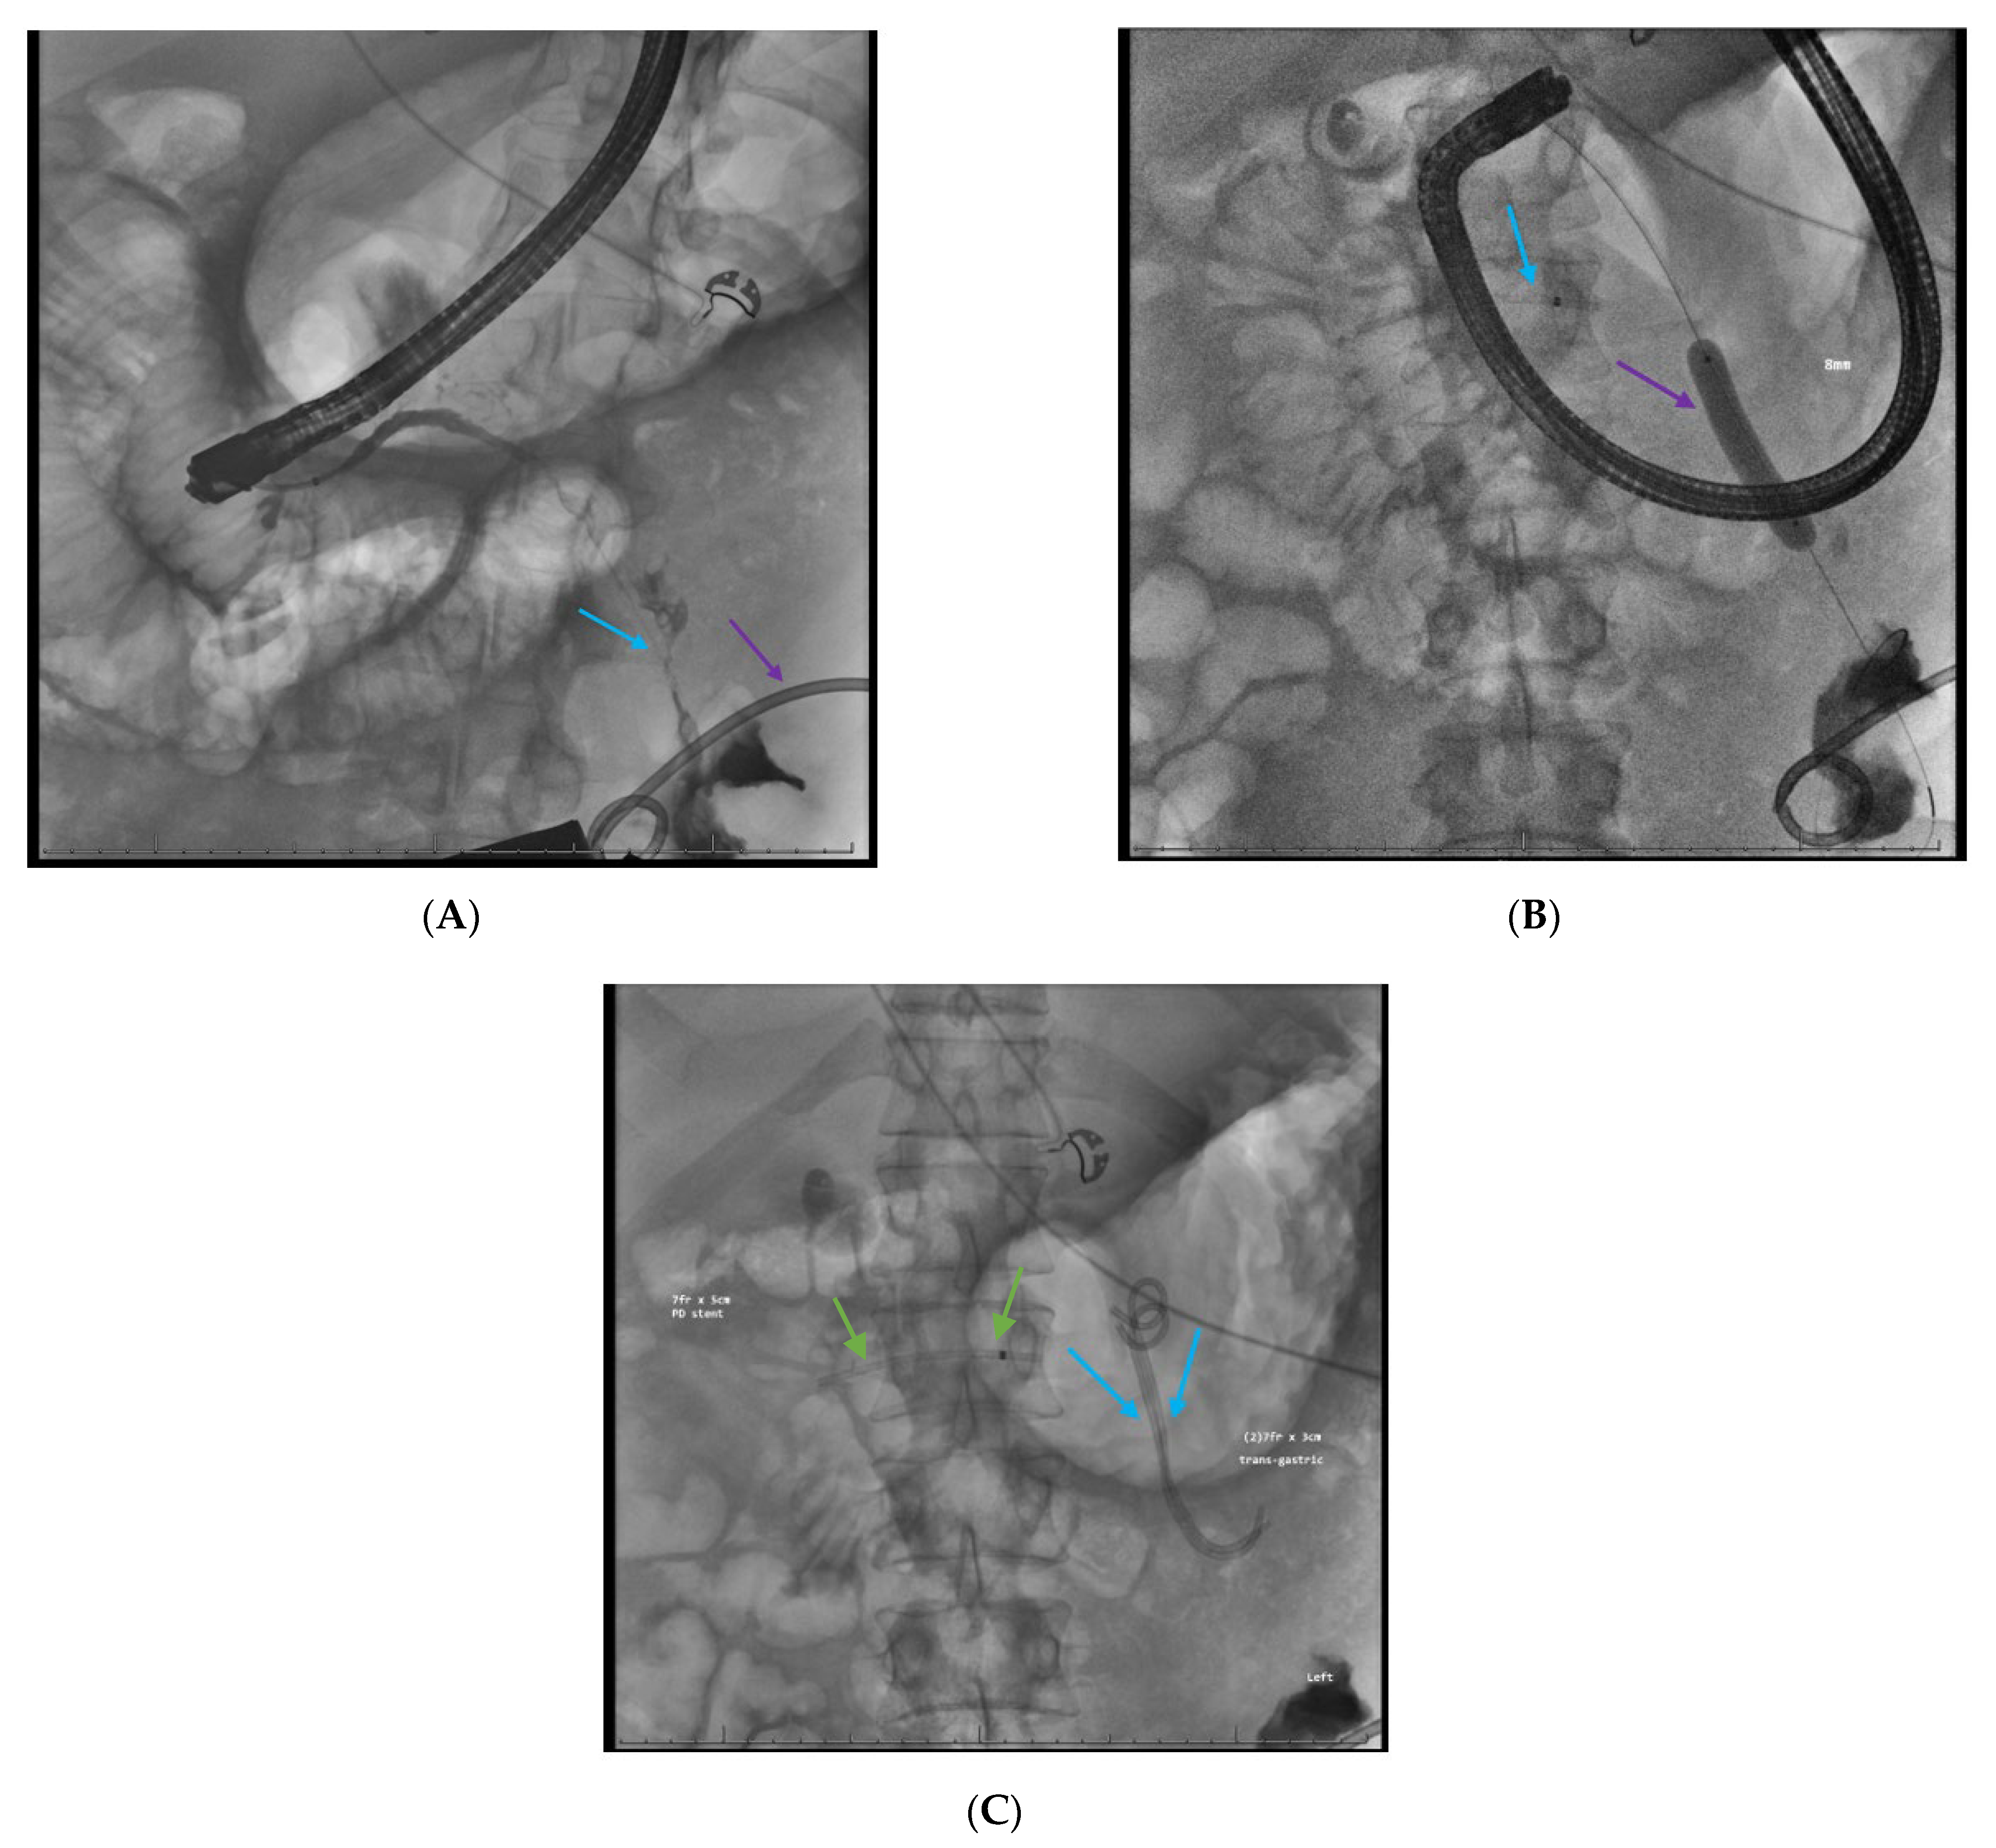

2.6. Dual Modality Drainage

2.9. Approach to Disconnected Pancreatic Duct Syndrome (DPDS) After Severe Pancreatitis